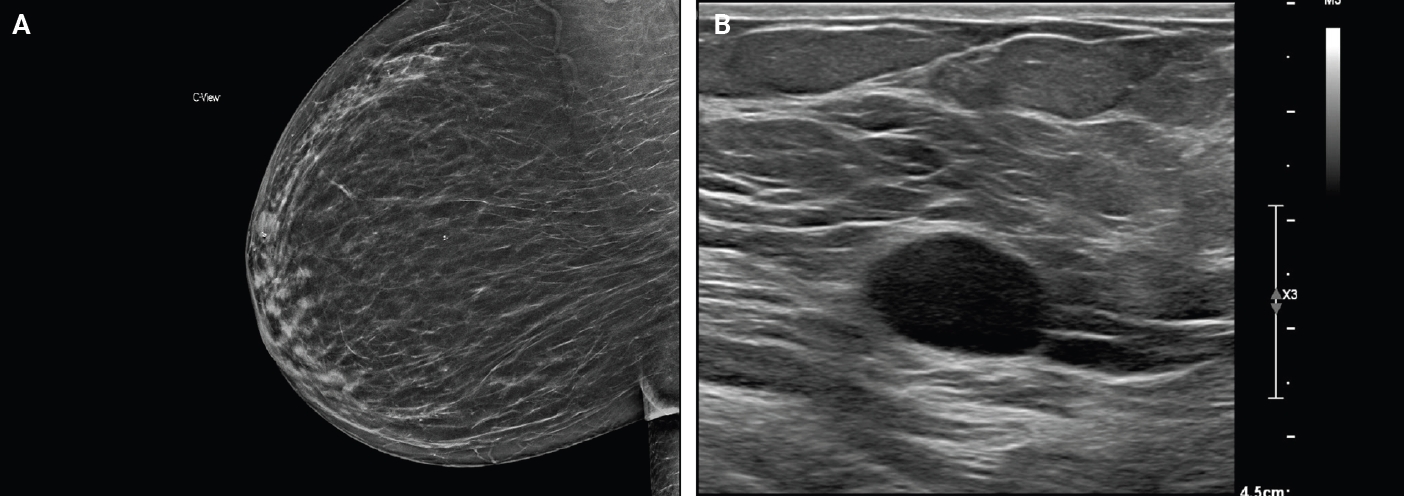

Breast schwannoma: review of entity and differential diagnosis

Schwannomas are benign peripheral nerve sheath tumors composed of Schwann cells, which uncommonly involve the breast. Most breast schwannomas are clinically present as a superficial palpable breast mass but may also be detected on screening mammography. Excision is the preferred treatment if symptomatic, and these are not known to recur. Histomorphology is similar to other anatomic sites: bland spindle cells with wavy nuclei, nuclear palisading (Verocay bodies), variably hypercellular (Antoni A) and hypocellular (Antoni B) areas, myxoid stroma, hyalinized vessels and variable cystic degeneration. Classic immunohistochemistry is diffuse and strong labeling for S100 and Sox10. Notable diagnostic pitfalls specific to the breast include myofibroblastoma, particularly the palisaded variant, and fascicular pseudoangiomatous stromal hyperplasia.